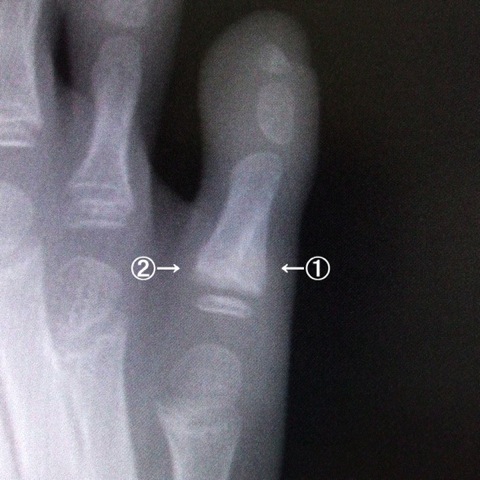

レントゲンを撮ったらこんな具合。

左が骨折してまだ整復(元にもどす事)する前、8月31日の写真、

右が今日撮った写真、治してから2ヶ月ちょっと経った写真です。

今日の写真を拡大してみると

①の少し色の薄い三角形の所が新しくできている骨。

それにつれて②の部分がどんどん吸収されていってます。

こうして自然に骨が元の状態にもどっていっていくらしい。